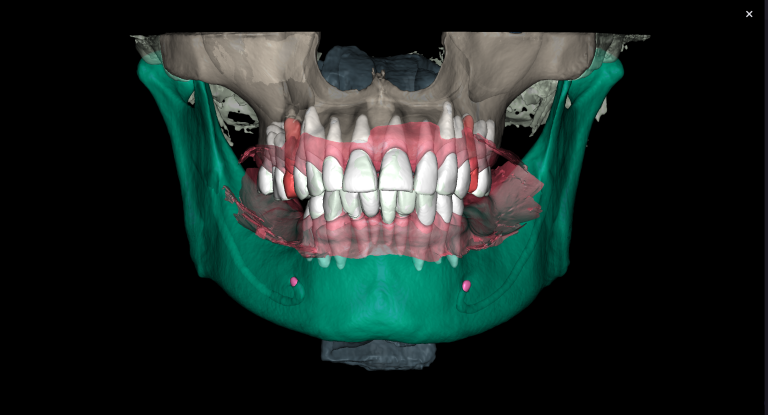

Diagnocat AI helps us to see not only the consequences, but also the causes of the pathology. For example, in this clinical case – the missed MB2 during previous endodontic treatment of tooth 26 (Universal 14)

The 3D-Viewer allows the clinician to align the axes according to the area of interest and to study root canal morphology and anatomy before starting a treatment